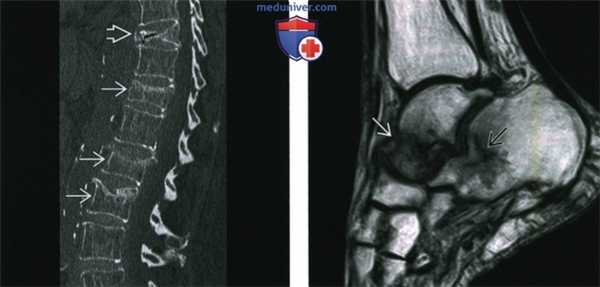

(Слева) Обзорная сагиттальная томограмма, поясничный отдел позвоночника пациента с тяжелым остеопорозом, осложненным множественными компрессионными переломами. В этом случае определяются клиновидные и взрывные переломы. Переломы у пациентов с остеопорозом являются основной причиной инвалидизации.

(Справа) На сагиттальной Т1ВИ МР-томограмме визуализируются типичные стрессовые переломы. Типичное место - шейка таранной кости. Задняя бугристость пяточной кости поражается чаще, чем тело. В этом случае имеются переломы обеих локализаций.